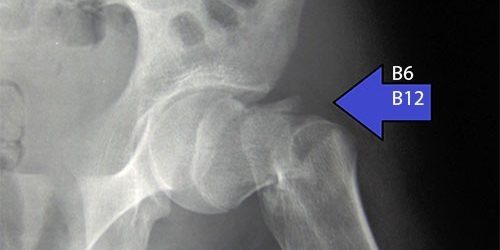

Согласно новому американскому исследованию, у пожилых женщин, которые принимают биологически активные добавки с высокими дозами витаминов B6 и B12, выше риск перелома бедра.

По сравнению с женщинами, у которых был наименьший уровень потребления обоих витаминов, у женщин, потреблявших их больше всего (не менее 35 мг B6 и 20 мкг B12), на 47% был выше риск перелома бедра. Половина женщин, принимавших участие в исследовании, ежедневно принимали не менее 3,6 мг B6 и 12,1 мкг B12.